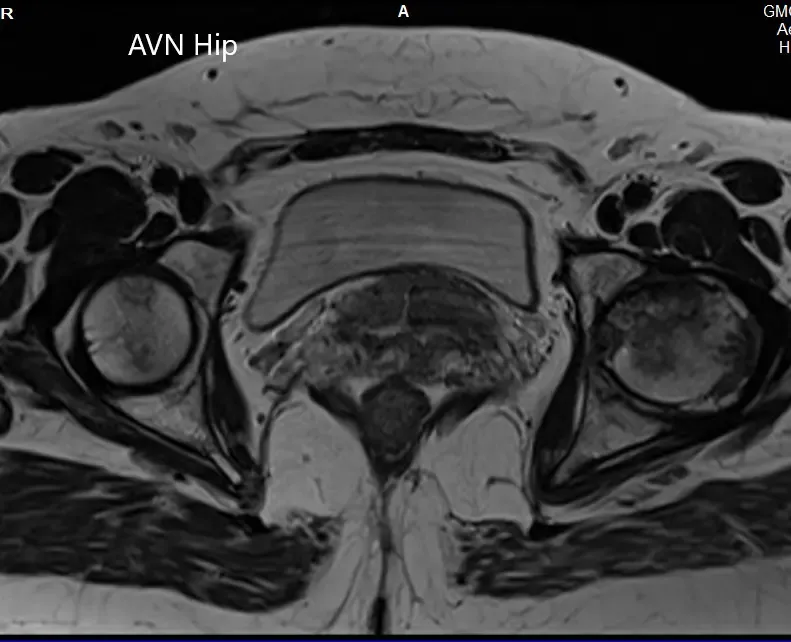

Se realizó una resonancia magnética que mostró una intensidad de señal alterada tanto en T1WI como en T2WI. Hubo un colapso sutil de la cabeza femoral izquierda. Se observó una línea sérpinosa e hiperintensa en T2WI que delimitaba una zona de osteonecrosis en la cabeza femoral izquierda. Esta zona afectaba al compartimento lateral y medial y cubría más del 50% de la superficie de la cabeza.

Se visualizaron cambios osteoartríticos secundarios en forma de reducción del espacio articular anterosuperior y formación de osteófitos. Se observó una pequeña cantidad de líquido en la cavidad articular.

T1WI y T2WI de la resonancia magnética muestran una sección axial de la cabeza femoral bilateral.